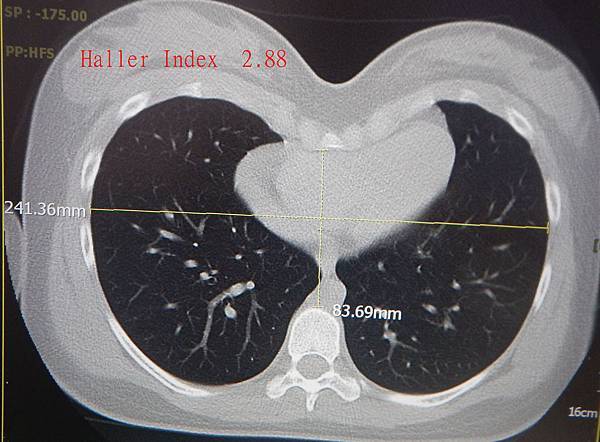

Haller index, 或稱凹陷指數, 常用於凹胸的嚴重度評估, 是由Dr.

Haller, Dr. Kramer, 及Dr. Lietman 在1987 創出來的方法, 即用簡單的公式, 即胸腔橫內徑除以內前後徑(胸骨至脊椎的距離), 所得的數值, 如一般人橫內徑是25公分, 前後內徑是10公分, Haller index 即是25/10=2.5 .

當時, 認為大於3.25即有手術矯治的必要.